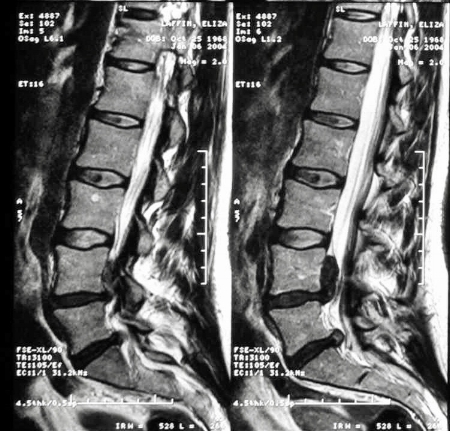

extrusions.jpg

The MRI showed a "huge" extrusion at L4-5, and a smaller one at L5-S1. The bigger one — L4-5 — looked like a black snake, crawling up my spinal canal, toward my brain. Later, the spinal surgeon will tell me it’s one of the largest he’s seen in over 30 years of practice. Another referred to it as "the mother of all extrusions."